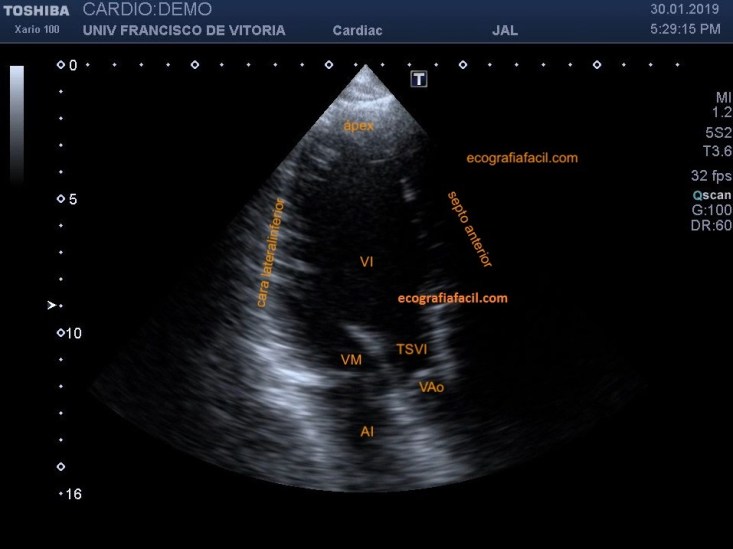

La utilidad de este plano es observar otras paredes del VI para objetivar otros segmentos de las paredes del VI y poder describir las alteraciones en la contracción segmentaria además de la contracción global (fig. 26). En el próximo post explicaremos la segmentación de las diferentes paredes y los territorios vasculares coronarios.

The usefulness of this plane is to observe other LV walls to objectify other segments of the LV walls and to be able to describe the alterations in the segmental contraction as well as the global contraction (Figure 26). In the next post we will explain the segmentation of the different walls and coronary vascular territories.

Además del estudio muscular, en este plano (que se parece al eje largo, pero con el corazón puesto de pie) se valora bien la patología de la válvula mitral que cursa con prolapso de la misma. Por este motivo hay que cuidar bien los parámetros para obtener una imagen de calidad y, llegado el caso, hacer un zoom selectivo sobre la válvula. Los prolapsos suelan dar insuficiencia con jet de pared que pueden escaparse e infravalorarse si no vamos a buscarlos específicamente.

Also the muscular study, in this plane (which resembles the long axis, but with the heart standing), the pathology of the mitral valve with prolapse of the mitral valve is well evaluated. For this reason, we must take good care of the parameters to obtain a quality image and, if necessary, selectively zoom in on the valve. Prolapses tend to give insufficiency with a wall jet that can escape and be underestimated if we do not specifically look for them.